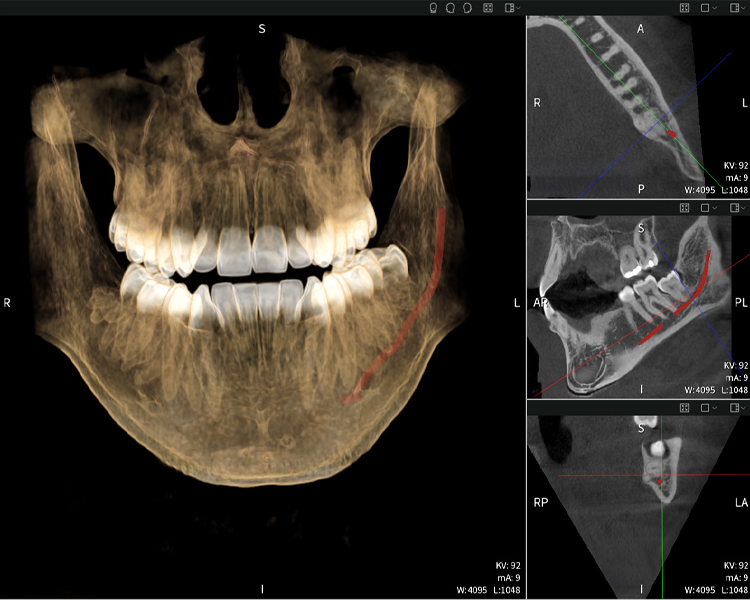

Figures b–d show various views of a 3D reconstruction of the mandible, providing a comprehensive overview of the mandibular anatomy, the position of the nerves in relation to the teeth, and allowing assessment of tooth symmetry and alignment.

Figure d shows the previously treated tooth 48, with its crown removed, and its roots left in proximity to the nerve, illustrating the high risk of nerve damage.